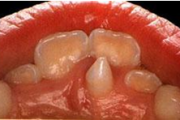

Laste ja noorukite söömishäired. Anorexia nervosa, Bulimia nervosa